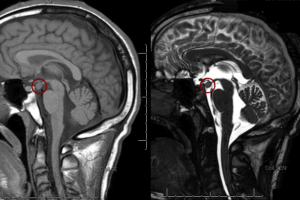

Hypothalamic Hemartoma and Gelastic Seizures

The MR images show an abnormal growth hanging down from the hypothalamus. This is a hypothalamic hemartoma, which in some cases can be a type of grey matter heterotopia within the tuber cinereum.... Read more »